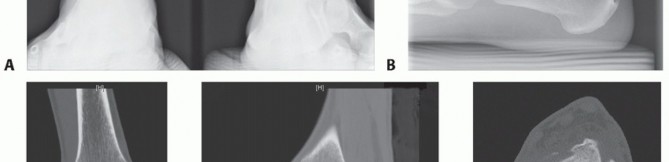

We routinely obtain simulated weight-bearing radiographs at 6 and 10 weeks and again at 14 to 16 weeks, depending on the progression of healing. If there was a concern about fixation of the graft or osteotomy, then radiographs are also obtained at the first postoperative visit (FIGS 1 , 2 and 3).

FIG 1 • Two-and-a-half-year follow-up. A. AP radiograph. B. Lateral radiograph. C. Clinical correlation.*

Gross et al2 reported on nine patients who underwent fresh osteochondral allograft transplantation. At a mean follow-up of 11 years, six grafts remained in situ. The three failed allografts demonstrated radiographic and intraoperative evidence of fragmentation or resorption, and these patients went on to ankle fusion. Standardized outcomes measures for comparison were not used in that study.

Raikin3 recently reported on 15 patients who underwent bulk fresh osteochondral allografting for large-

volume cystic lesions of the talus. The mean volume of the cystic lesions was 6059 mm3. At a mean followup of 4.5 years, the mean American Orthopaedic Foot and Ankle Society (AOFAS) ankle-hindfoot score was 83 points. Only two grafts failed and went on to have an ankle arthrodesis. Some form of graft collapse, graft resorption, or joint space narrowing was seen in all patients.

A retrospective review by Adams et al1 showed significant improvement in pain and the Lower Extremity Functional

Score (LEFS) at a mean follow-up of 48 months in eight patients who underwent osteochondral allograft transplantation of the talus. The mean postoperative AOFAS anklehindfoot score was 84 points. Three grafts were found to have graft-host lucencies in one plane on plain radiography. These patients were doing well and no further imaging was obtained. One patient continued to be symptomatic and was thought to have a nonunion of the graft due to circumferential lucency. Second-look arthroscopy demonstrated partial graft cartilage delamination but a stable graft. The patient did not wish to have any further treatment.

FIG 2 • Dorsiflexion. A. Radiograph (although the joint appears to narrow anteriorly, this phenomenon has not changed in 2 years and the patient experiences no pain or impingement). B. Clinical appearance.*

FIG 3 • Plantarflexion. A. Radiograph. B. Clinical correlation.*